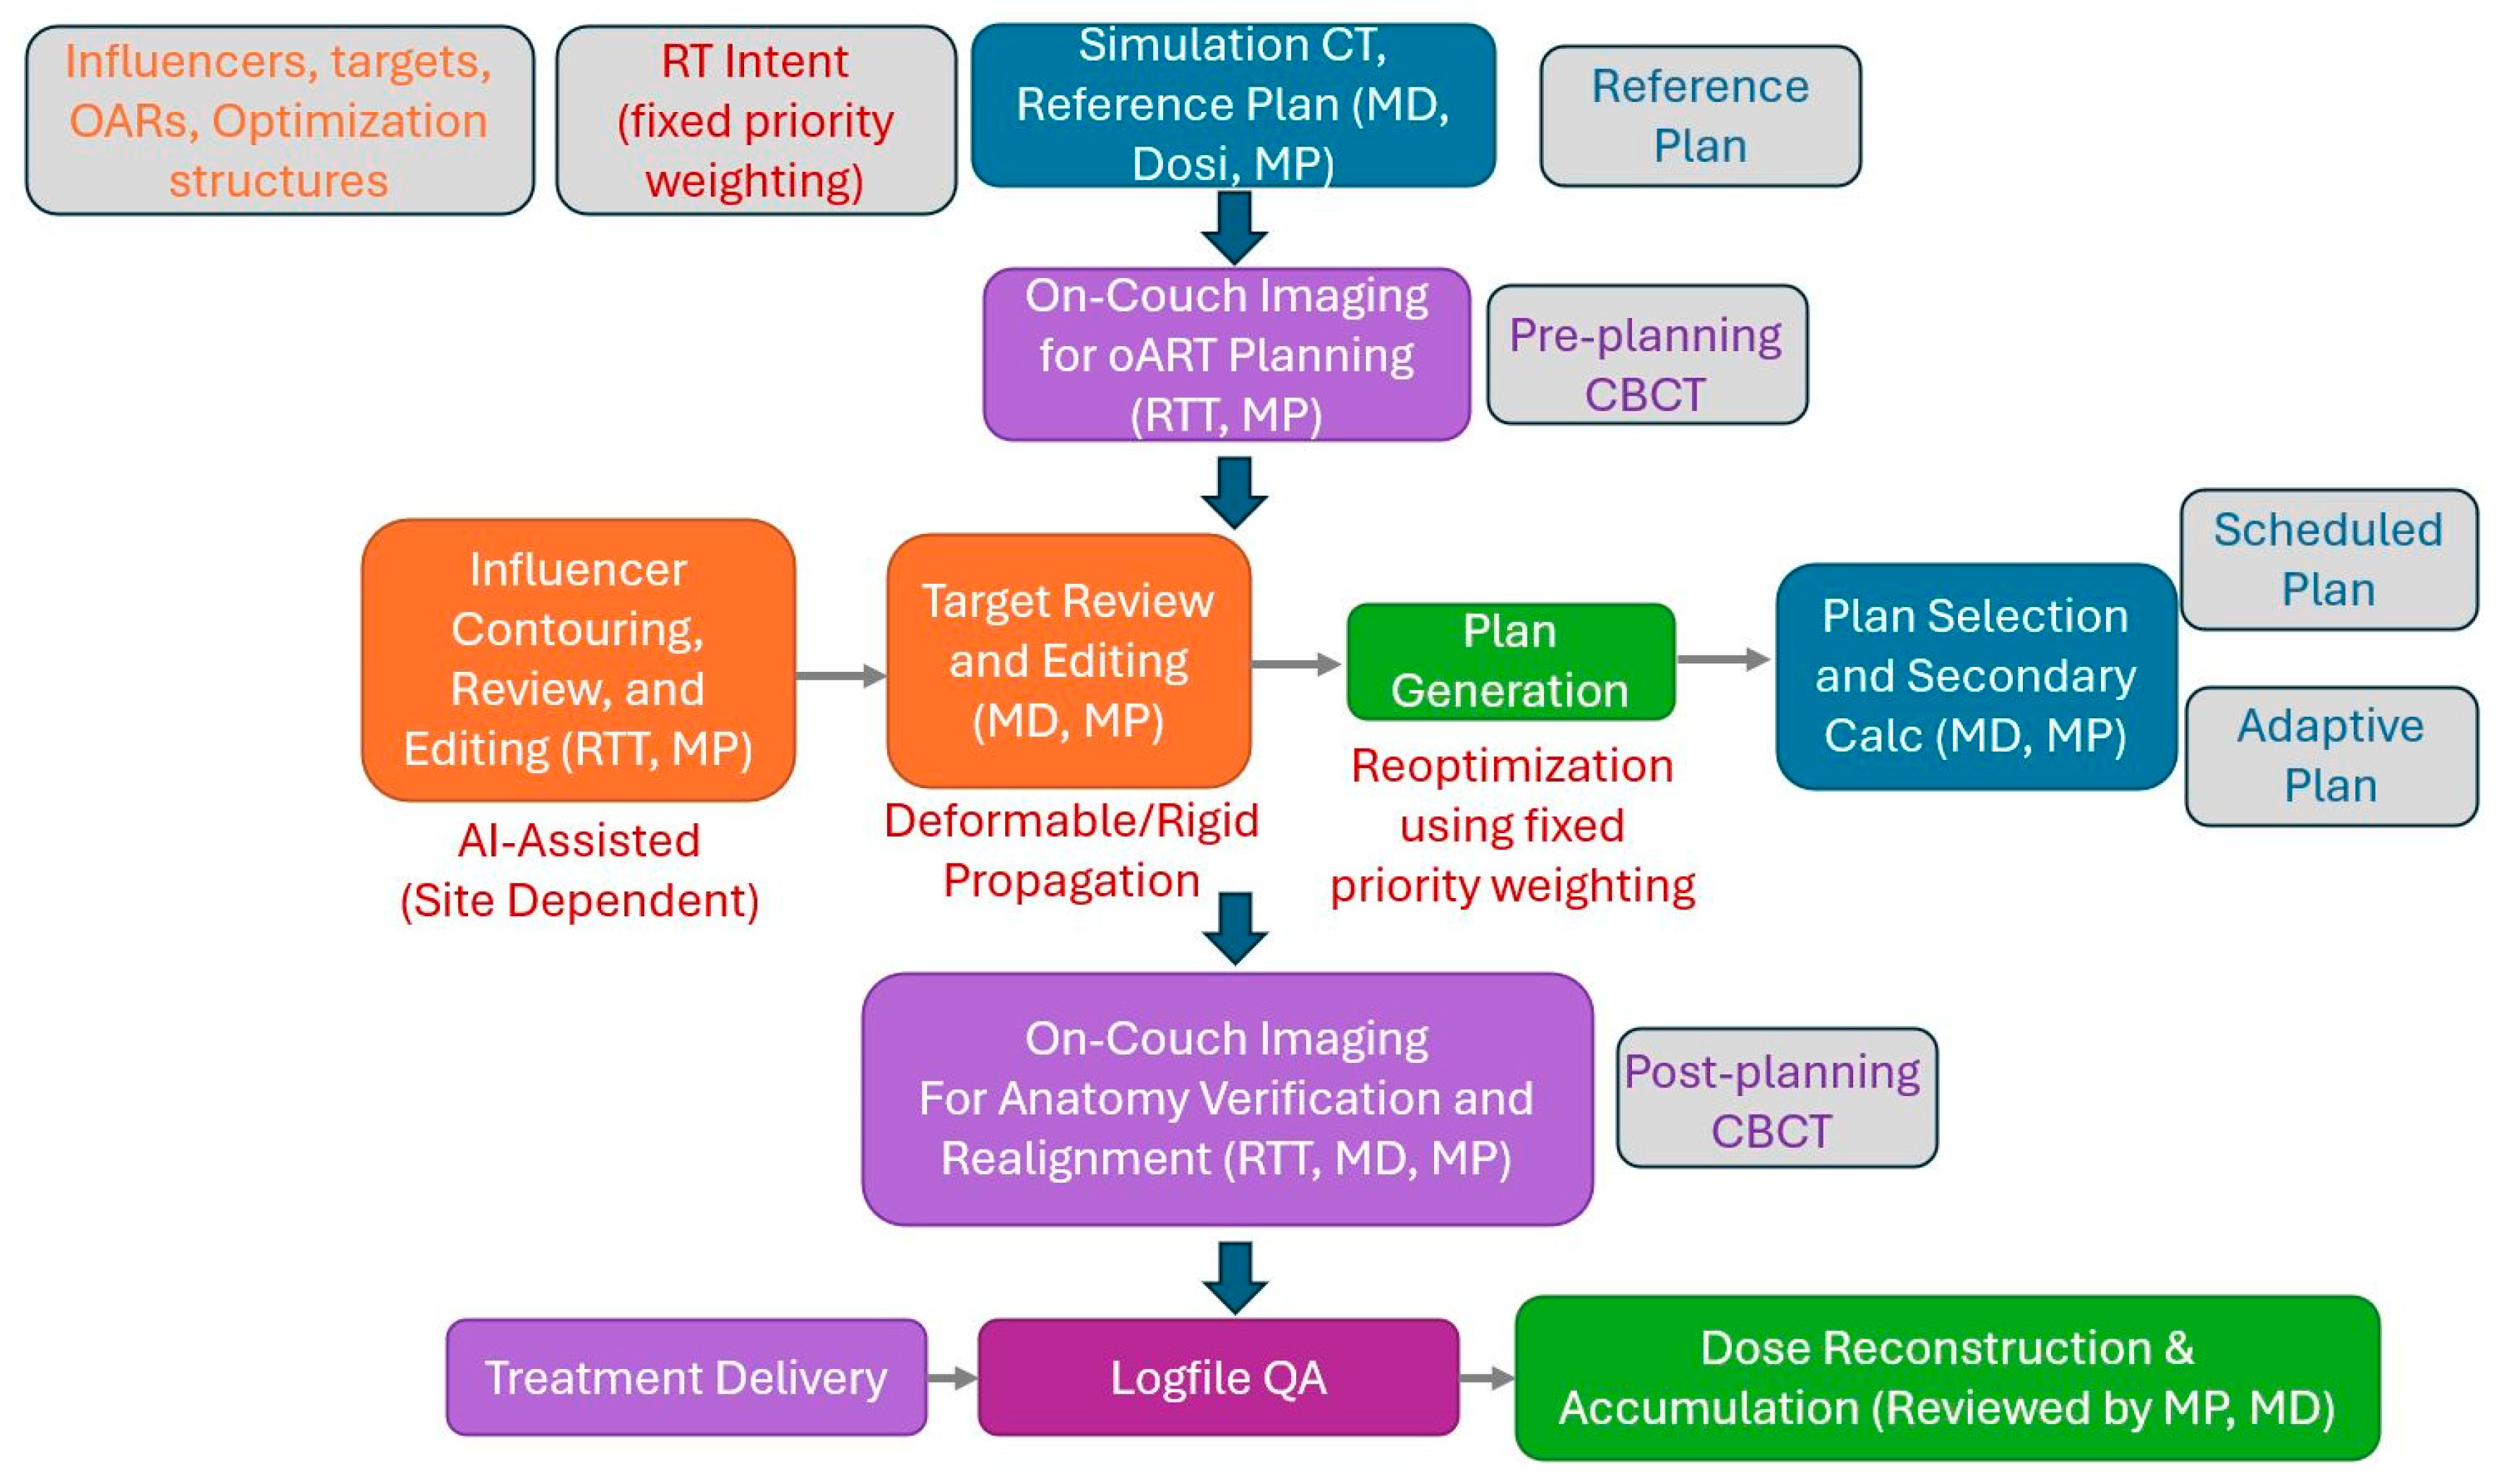

2.1. Overview of the Reviewed Pelvic oART Cases and Our Adaptive Workflow

2.2. Multidisciplinary Approach and Retrospective Review Methodology